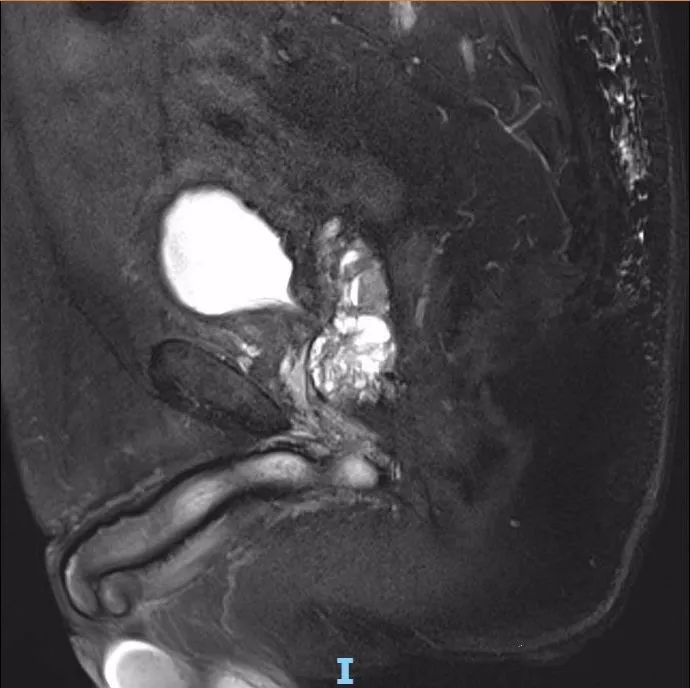

术后一年半,李先生又到医院复查,前列腺大小已减少至20g,各项指标也都显示正常。

△ 术后核磁共振成像